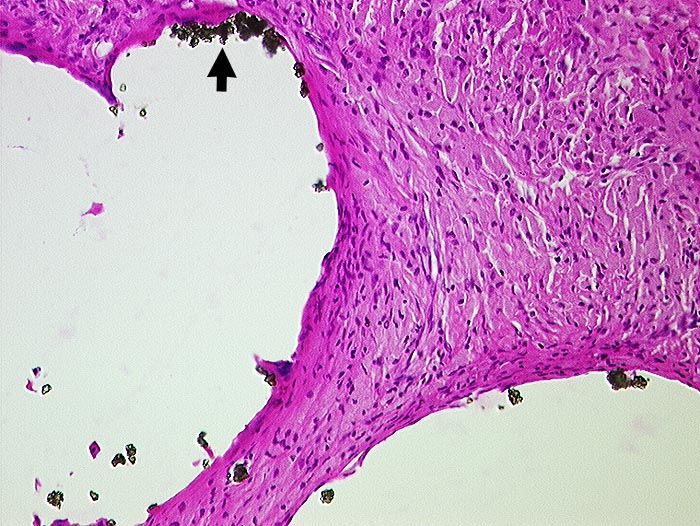

Zementabrieb

Artefakt / Fremdkörper / Pigment

Weichteile Hüfte

Weichteile

Vernarbtes geringgradig entzündlich infiltriertes Gewebe aus dem Pfannengrund. In grossen Hohlräumen liegen

►

Bariumpartikel. Der Zement ist durch die Verarbeitung herausgelöst worden.

Klinik

Hüft-TP Wechsel.